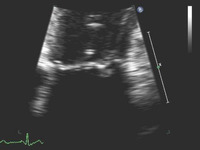

Mitral valve P2 leaflet prolapse: 2D view

From the collection of Prakash P. Punjabi